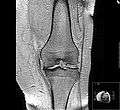

MRI of osteoarthritis in the knee, with characteristic narrowing of the joint space.